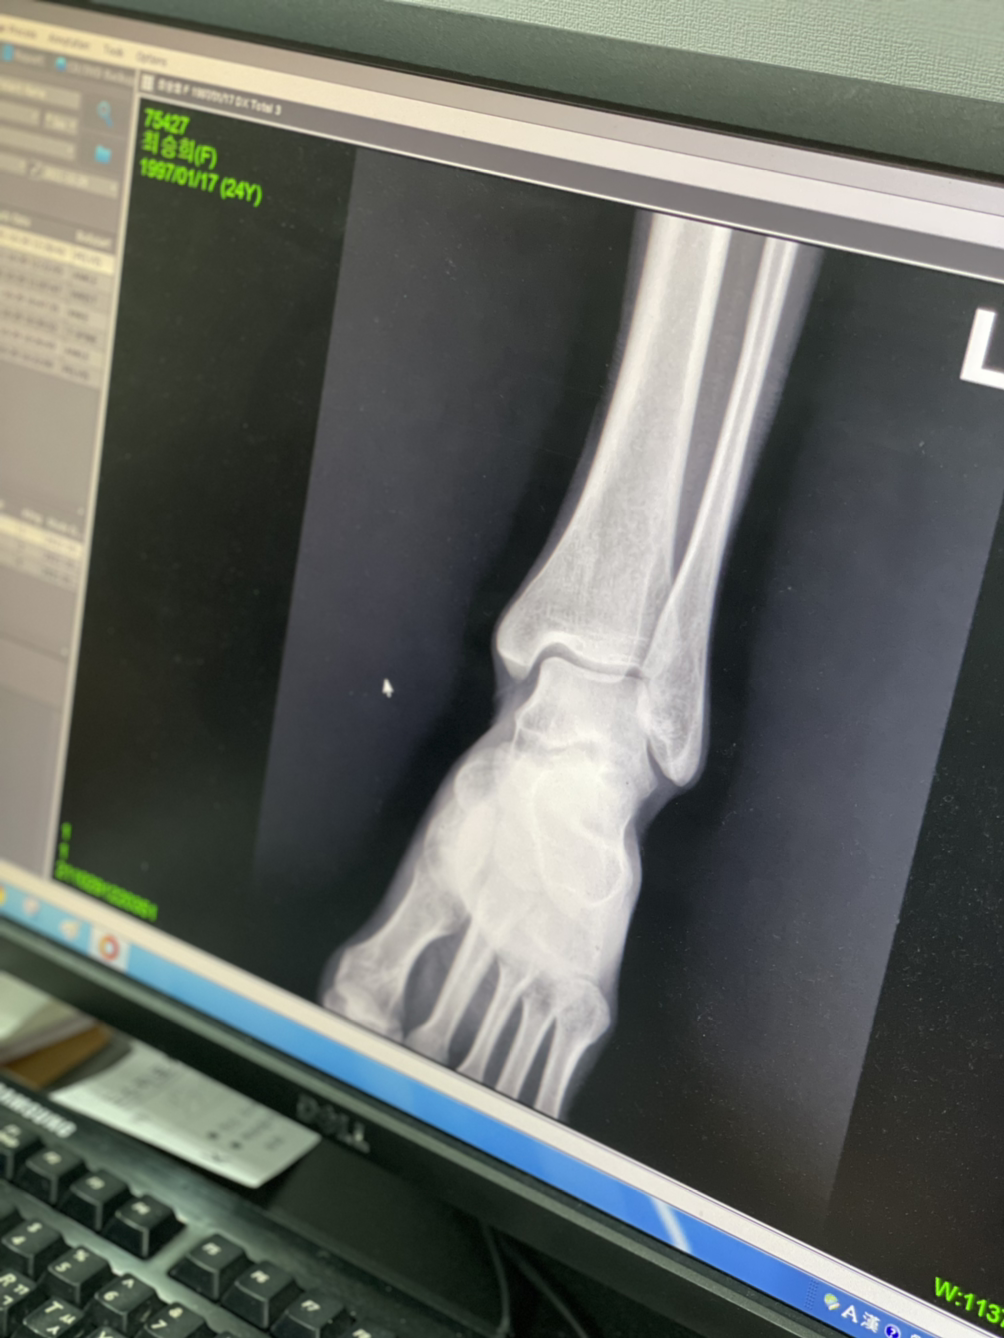

아플땐 쉬어가자 ㅎ ..아킬레스건염이라네..^^..

골반이 삐뚤어졌대

종형외과...

넘비싸...8ㅅ8 근데 너무아프고...ㅋㅋㅋ 많이 삐둘어지긴한듯